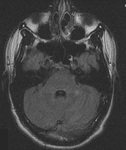

RNM cranioencefálica: o sinal pulvinar (um termo que se refere à hiperintensidade pulvinar bilateral) em um paciente com doença de Creutzfeldt-Jakob em imagens ponderadas por difusão

Do acervo pessoal de Leo H. Wang; usado com permissão